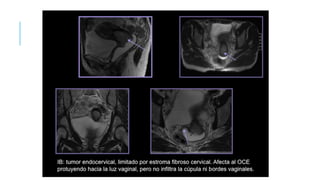

ESTADIFICACION

TC Y RM pudiéndose objetivar la obstrucción ureteral extrínseca, la invasión vesical y rectal,

la presencia de adenopatías y la propagación a nivel extrapélvico. Asu vez, por estos

métodos, pueden monitorearse el tratamiento y la recurrencia del tumor.

Los factores más importantes a tener en cuenta en el informe de los estudios por imágenes

deben incluir:

1) Tamaño del tumor.

2) Profundidad de la invasión miocervical.

3) Grado de extensión de la invasión parametrial (parametrios laterales y uterosacros),

informando si llega hasta la pared pelviana.

4) Presencia de infiltración vaginal.

5) Evaluación de los ganglios linfáticos pelvianos y/o lumboaórticos desde la fosa obturatriz.

6) Evaluación de la infiltración del espacio vésicocérvico- vaginal y/o del espacio recto-vaginal.

7) Evaluación de posibles metástasis a distancia.

ESTADIFICACION TC Y RMpudiéndose objetivar la obstrucción ureteral extrínseca, la invasión vesical y rectal, la presencia de adenopatías y la propagación a nivel extrapélvico. Asu vez, por estos métodos, pueden monitorearse el tratamiento y la recurrencia del tumor. Los factores más importantes a tener en cuenta en el informe de los estudios por imágenes deben incluir: 1) Tamaño del tumor. 2) Profundidad de la invasión miocervical. 3) Grado de extensión de la invasión parametrial (parametrios laterales y uterosacros), informando si llega hasta la pared pelviana. 4) Presencia de infiltración vaginal. 5) Evaluación de los ganglios linfáticos pelvianos y/o lumboaórticos desde la fosa obturatriz. 6) Evaluación de la infiltración del espacio vésicocérvico- vaginal y/o del espacio recto-vaginal. 7) Evaluación de posibles metástasis a distancia.

• #32 La clasificación de las etapas clínicas de la evolución del carcinoma de cuello, partiendo de la etapa cero, que correspondería al carcinoma in situ (CIN-III o HSIL):2 Estadio I: confinado al cuello del útero. Con un estadio IA si el tumor mide menos de 7 mm de superficie y 5 mm de invasión en profundidad; y un estadio IB si el tumor mide más o es macroscópico. Estadio II: se extiende más allá del cuello, pero no se extiende a la pared de la pelvis y, si afecta a la vagina, no llega a su tercio inferior. Se clasifica como IIA si no afecta a parametrios (IIA1 si es menor de 4 cm y IIA2 si es mayor) y IIB si los afecta. Estadio III: el carcinoma se extiende a la pared pelviana. En la exploración al tacto rectal no existe espacio entre el tumor y la pared pelviana; el tumor se extiende además al tercio inferior de la vagina. Sería un estadio IIIA si afecta al tercio inferior de la vagina, y un IIIB si afecta pared pélvica o tiene repercusión sobre el riñón. Estadio IV: estadio metastásico local (puede infiltrar la pared de la vejiga urinaria o el recto) (IVA) o a distancia (IVB), por ejemplo si aparecen en los pulmones.